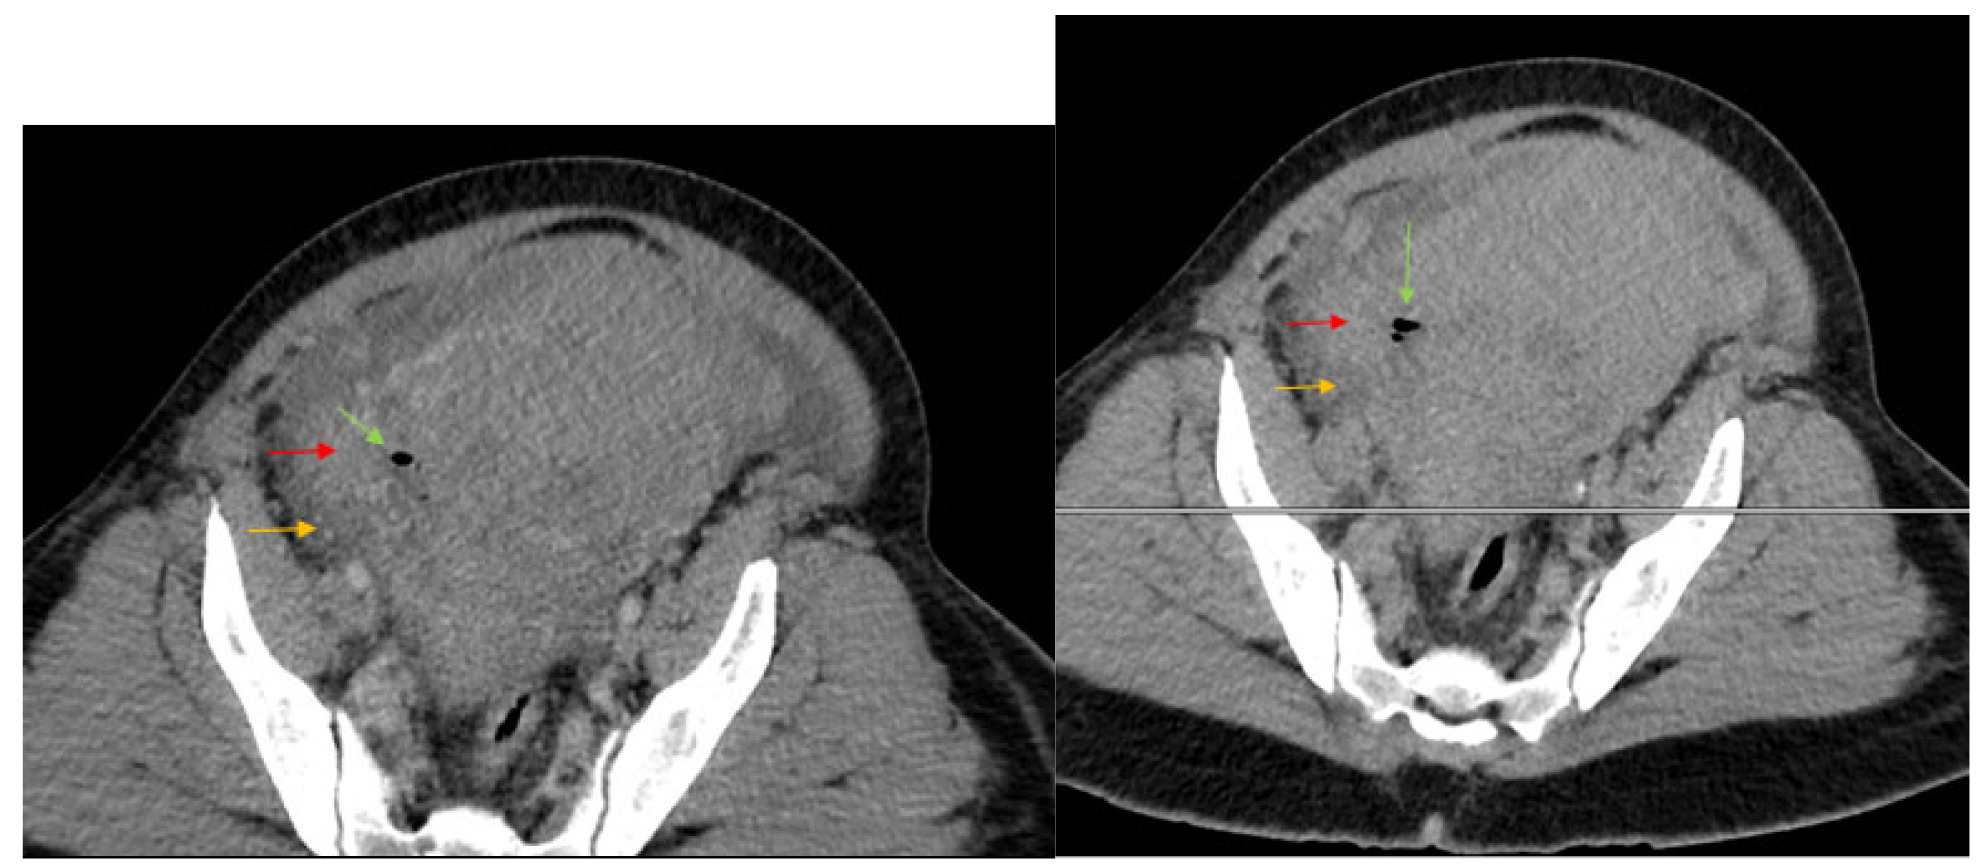

The initial impressions of the axial and coronal CT images revealed dilation of the right ovarian vein in addition to intraperitoneal fluid accumulation on the right side (Fig. 1-2). Portovenous and delayed phase images did not demonstrate contrast pooling or persistent hyperattenuation to suggest hyperacute hemorrhage (Fig. 3-4). Additionally, there was evidence of peritoneal air present between the uterine myometrium and ovarian vasculature most notable along the right aspect of the anterior inferior uterus. A contour abnormality along the right parasagittal lower uterine segment was also noted and interpreted as a uterine defect without signs of free intraperitoneal hemorrhage. In conjunction with her clinical picture, these radiologic findings raised our suspicion for a contained uterine rupture although there were no pathognomonic imaging findings to confirm an associated retroperitoneal hematoma. The patient was urgently taken to the operating room for an exploratory laparotomy to confirm the diagnosis and to manage surgically if indicated.

Uterine rupture was highly suspected even prior to the exploratory laparotomy due to the presence of air between the uterine myometrium and the ovarian vessels. Figures 1-4 describe CT findings consistent with uterine rupture. This is the first case report of a uterine rupture being managed conservatively similarly to previously described management options for contained uterine hematomas.